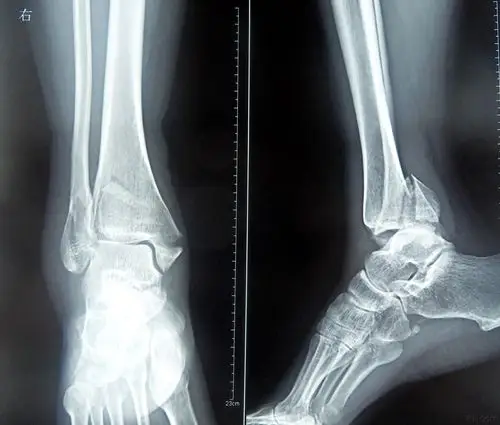

典型踝关节骨折的治疗讨论

甘肃省人民医院骨一科杨青山副主任医师团队:踝关节骨折

原始片(外院3.13)